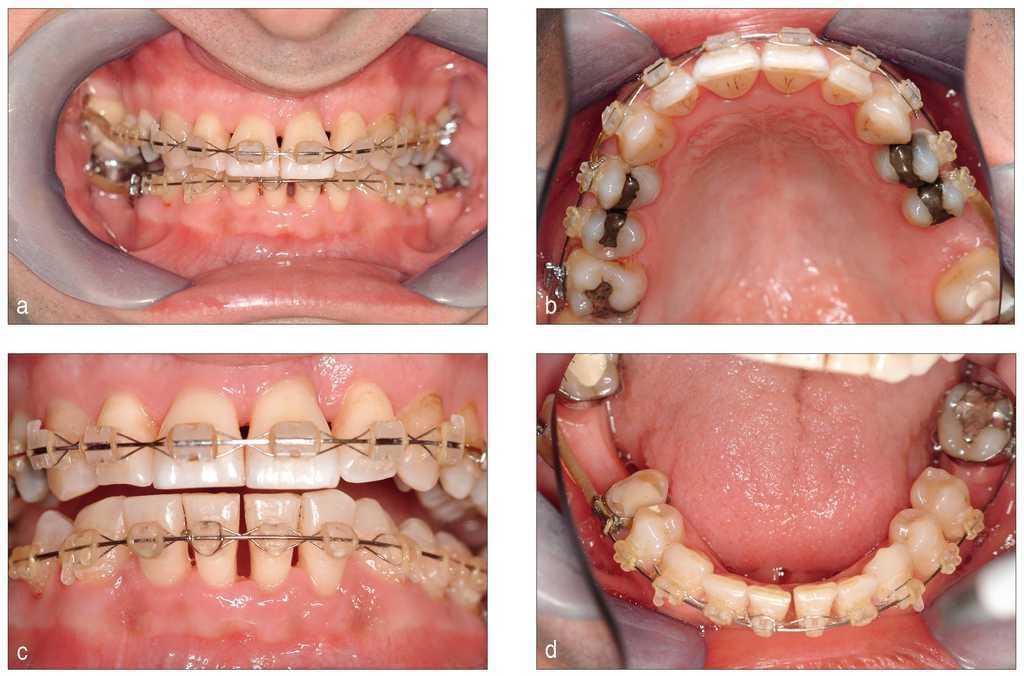

Uno o dos años después de iniciar el tratamiento, el cuadro es clínicamente y radiológicamente estable con una ganancia de inserción clara y profundidades de sondaje fisiológicas incluso en los dientes 31 y 21, cuyo pronóstico inicial era desfavorable (figs. 7 y 8a a 8c). El odontólogo que derivó al paciente puede asumir a partir de este momento el tratamiento restaurador posterior.

Figura 8. Situación clínica dos años después del inicio del tratamiento: se aprecia un periodonto estable sin alteraciones.